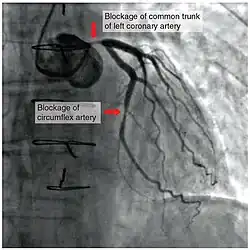

To diagnose a coronary occlusion, a doctor may view a patient's medical history, or perform a coronary angiography; a doctor will stick a catheter into the wrist or groin, lead it to the heart, and inject a liquid for X-ray imaging.[4]